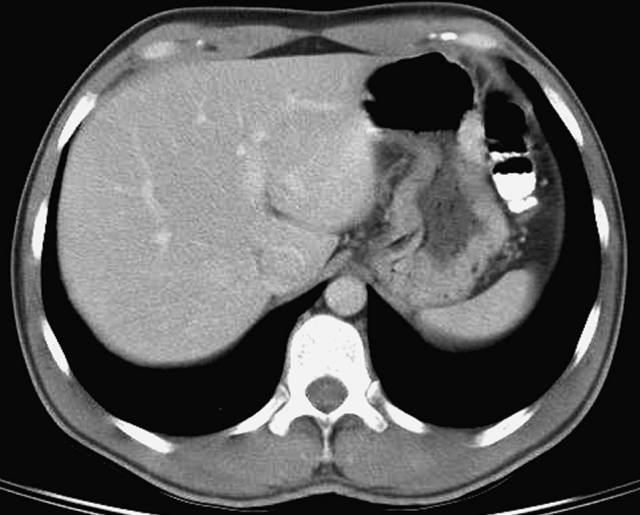

第二层

腹腔(粉色);腹膜后(黄色)

1、肝右叶;2、下腔静脉;3、肝尾状叶;4、肝门静脉;5、肝左叶;6、胃左动脉;7、腹直肌;8、膈肌;9、胃;10、结肠左曲;11、腹外斜肌;12、胸导管;13、奇静脉;14、腹主动脉;15;胸椎;16、最长肌;17、椎管和脊髓;18、棘肌;19、髂肋肌(胸段);20、脾脏;21、左肺;22、背阔肌;23、肋膈隐窝;24、右膈下隐窝;25、肝裸区;26、膈上淋巴结;27、肋间淋巴结;28、后纵隔;29、膈下淋巴结;30、左侧结肠旁沟。